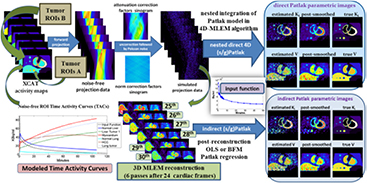

Whole-body (WB) dynamic PET has recently demonstrated its potential in translating the quantitative benefits of parametric imaging to the clinic. Post-reconstruction standard Patlak (sPatlak) WB graphical analysis utilizes multi-bed multi-pass PET acquisition to produce quantitative WB images of the tracer influx rate Ki as a complimentary metric to the semi-quantitative standardized uptake value (SUV). The resulting Ki images may suffer from high noise due to the need for short acquisition frames. Meanwhile, a generalized Patlak (gPatlak) WB post-reconstruction method had been suggested to limit Ki bias of sPatlak analysis at regions with non-negligible 18F-FDG uptake reversibility; however, gPatlak analysis is non-linear and thus can further amplify noise. In the present study, we implemented, within the open-source software for tomographic image reconstruction platform, a clinically adoptable 4D WB reconstruction framework enabling efficient estimation of sPatlak and gPatlak images directly from dynamic multi-bed PET raw data with substantial noise reduction. Furthermore, we employed the optimization transfer methodology to accelerate 4D expectation–maximization (EM) convergence by nesting the fast image-based estimation of Patlak parameters within each iteration cycle of the slower projection-based estimation of dynamic PET images. The novel gPatlak 4D method was initialized from an optimized set of sPatlak ML-EM iterations to facilitate EM convergence. Initially, realistic simulations were conducted utilizing published 18F-FDG kinetic parameters coupled with the XCAT phantom. Quantitative analyses illustrated enhanced Ki target-to-background ratio (TBR) and especially contrast-to-noise ratio (CNR) performance for the 4D versus the indirect methods and static SUV. Furthermore, considerable convergence acceleration was observed for the nested algorithms involving 10–20 sub-iterations. Moreover, systematic reduction in Ki % bias and improved TBR were observed for gPatlak versus sPatlak. Finally, validation on clinical WB dynamic data demonstrated the clinical feasibility and superior Ki CNR performance for the proposed 4D framework compared to indirect Patlak and SUV imaging.

Recently, we proposed a clinically adoptable dynamic WB 18F-FDG PET data acquisition framework involving a streamlined 6-pass WB protocol (Karakatsanis et al 2013a, 2013c). In that framework, the dynamic WB PET images were first reconstructed, using a regular 3D maximum-likelihood expectation–maximization (ML-EM) algorithm (Dempster et al 1977, Shepp and Vardi 1982). Then, the standard Patlak (sPatlak) linear graphical analysis method (Patlak et al 1983) was employed on the voxel level to robustly estimate images of the tracer influx rate constant Ki and the blood distribution volume V. As sPatlak considers a linear relationship between the estimated parameters and the measured data, the ordinary least squares (OLS) regression method was applied to robustly fit the images to the model.

Here we propose a multi-bed extension of the previous nested 4D sPatlak algorithms to directly and efficiently reconstruct sPatlak WB images from dynamic WB PET raw data at an accelerated convergence rate. In addition, we present a novel non-linear 4D nested gPatlak reconstruction algorithm for quantitative WB Ki imaging either in single- or multi-bed FOVs, including regions where linear sPatlak yields biased Ki estimates, due to non-negligible uptake reversibility. Both methods are based on our previously optimized 6-pass WB scan protocol corresponding to 0–45 min post injection (p.i.) scan window. By acquiring six WB passes, the necessary temporal data redundancy is attained to facilitate (a) kinetic-driven optimization of the acquisition time window, and (b) robust estimation of Patlak parametric images, especially for gPatlak non-linear parameters. Finally, we introduce a practical sPatlak-based initialization scheme for the gPatlak 4D algorithm to potentially overcome convergence problems to local optima, due to high noise in the data (Wu 1983). All proposed and reference algorithms have been implemented and validated on the open-source Software for tomographic image reconstruction (STIR) platform (Thielemans et al 2012) by building upon existing non-nested sPatlak reconstruction libraries (Tsoumpas et al 2008a) and including both simulated and clinical studies. As we target clinical adoptability, we laid emphasis on efficiency, robustness and application scope for the proposed methods.

The proposed WB dynamic PET data acquisition protocol consists of an initial dynamic PET scan at the cardiac bed position, immediately following tracer administration (first phase), namely 0–6 min p.i., to measure the rapidly changing early section of the tracer concentration in the blood plasma (input function). Then, a dynamic series of 6 WB passes follows (second phase), for 8–45 min p.i. (figure 1), to sample the later part of the tissue time activity curves (TACs) at every voxel across the WB FOV. The protocol has been streamlined for straightforward clinical adoption: each dynamic WB frame is scanned along the same axial direction (cranio-caudal or vice versa) and consists of equal number of beds of equal duration resulting in uniform temporal sampling rates for all bed positions (Karakatsanis et al 2013a).

Figure 1. Flow chart illustrating the sequence of all dynamic bed frames, as acquired with the step-and-shoot mode during the 2nd phase of the suggested WB dynamic PET protocol. In the example, 6 unidirectional (cranio-caudal) WB passes are acquired, each comprised of 7 beds of equal scan duration. Later the parametric Ki image at each column, i.e. bed position, is directly estimated via 4D sPatlak and gPatlak algorithms from the image-derived input function and the respective dynamic projection PET data.

Standard image High-resolution imageInitially, the PET 4D raw data from both protocol phases are independently reconstructed and the input function is extracted from regions-of-interest (ROIs) placed over the heart left-ventricle (LV) in the resulting PET dynamic images. The ROIs are drawn such that partial volume effects are minimized (Karakatsanis et al 2013a). Subsequently, the image-derived input function is utilized to produce WB parametric Ki images with (a) our previously validated indirect Patlak analysis and (b) the newly proposed direct 4D Patlak reconstruction methods.

Later, analytic simulations were conducted by forward projecting the emission images with STIR (Thielemans et al 2012) using the Biograph mCT system geometry (Jakoby et al 2011). Then, the generated sinograms were attenuated, according to the XCAT attenuation factors, and scaled based on a factor accounting for the sensitivity of the mCT scanner and the time frame duration. Quantitative Poisson noise was then added. Finally, the generated noise-free and noisy dynamic PET projection data were all reconstructed in either 3D or 4D mode, using current and newly developed STIR ML-EM libraries to produce dynamic PET and Patlak parametric images, respectively. A diagram illustrating the design of the simulated study, along with examples of reconstructed Patlak images, is presented in figure 4.

Figure 4. Diagram illustrating the steps for generating realistic simulation data of quantitative levels of noise and the subsequent reconstruction analysis to compare direct 4D versus indirect (s/g)Patlak imaging methods.

The noise-free dynamic PET SUV cardiac images in figure 5(a) (1st row) illustrate the variability introduced to each simulated lesion uptake and contrast during the first 45 min p.i. due to the modeled kinetics (table 1). The simulated dynamic PET images were produced from 3D ML-EM reconstruction (3 cycles of 21 iterations each) of dynamic cardiac data which were sampled according to our validated WB dynamic PET protocol (figure 1). Moreover, the reconstructed noise-free indirect and direct (s/g)Patlak Ki images in the 2nd row of figure 5(a) converged to higher lesion TBR contrast scores than any of the dynamic noise-free PET images for both ROI groups A and B. Therefore, in the absence of noise, Patlak may theoretically offer information beyond SUV and thus the complementary application of the two may enhance lesion detectability performance.

Figure 5. (a) Overview of noise-free Ki and kloss images and (b) noisy Ki images from simulated 4D PET data employing indirect and direct (s/g)Patlak methods. The orange and green bars denote sPatlak and gPatlak ML-EM global iterations respectively for the images directly above. In the last 2 rows, the yellow arrow position between the two bars designates at which iteration were the gPatlak estimates, on the right, initialized from the sPatlak estimates, on the left. (c) Quantitative Ki noise-bias trade-off analysis on four ROIs across 20 noise realizations. The red and green colors correspond to sPatlak and gPatlak methods, while the continuous and dotted delineations indicate direct and indirect methods, respectively. The triangle markers on red curves denote non-nested sPatlak method. Evaluations were conducted every 21 global ML-EM iterations, each consisting of 20 nested sub-iterations. Thus, gPatlak-4D was initialized after 3 × 21 = 63 sPatlak ML-EM iterations.